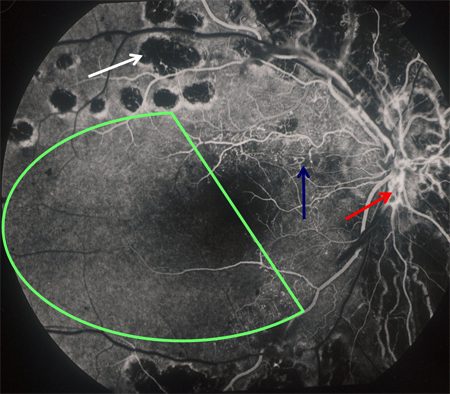

[Figure caption and citation for the preceding image starts]: Angiografía con fluoresceína en la retinopatía diabética proliferativa con isquemia macular: isquemia macular (círculo verde), ausencia de perfusión capilar (flecha blanca), nuevos vasos sanguíneos en la papila óptica (flecha roja), rosario venoso (flecha azul)Cortesía del Archivo Fotográfico de Moorfields; usado con autorización [Citation ends].